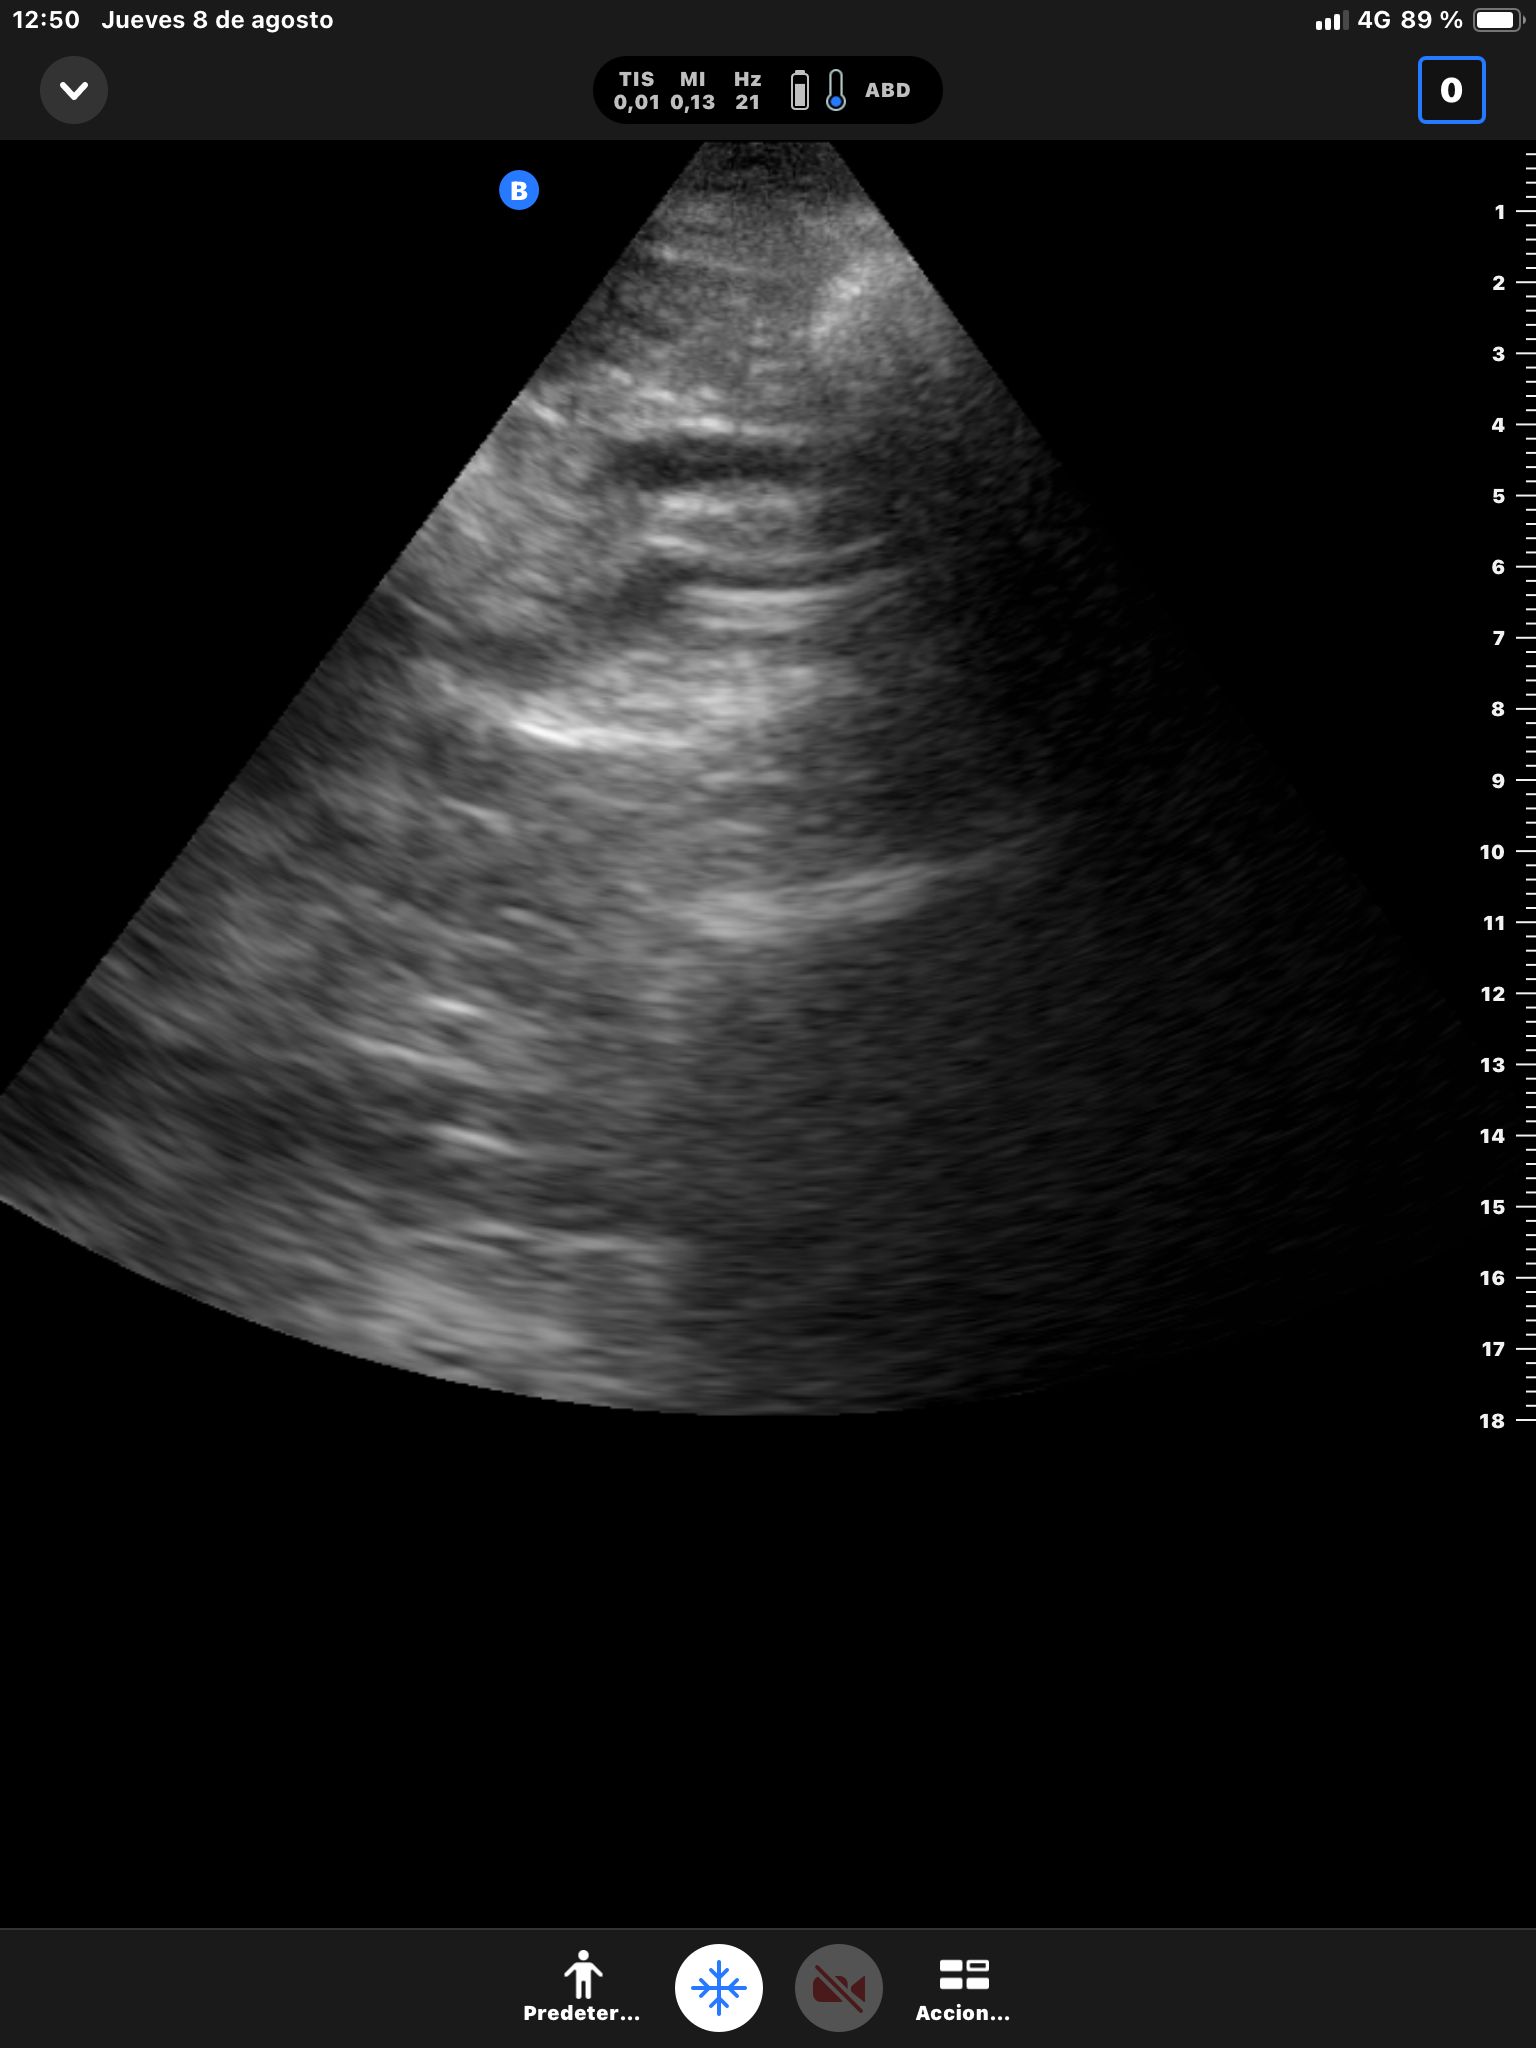

Se realiza ecografía abdominal.

Descripción de los hallazgos ecográficos y las imágenes más relevantes para la resolución del caso

Hígado sin LOEs. Vesícula biliar con hidrops (58 mm), dilatación del colédoco (10 mm). Páncreas hiperecogénico, atrófico, Wirsung de 76 mm.